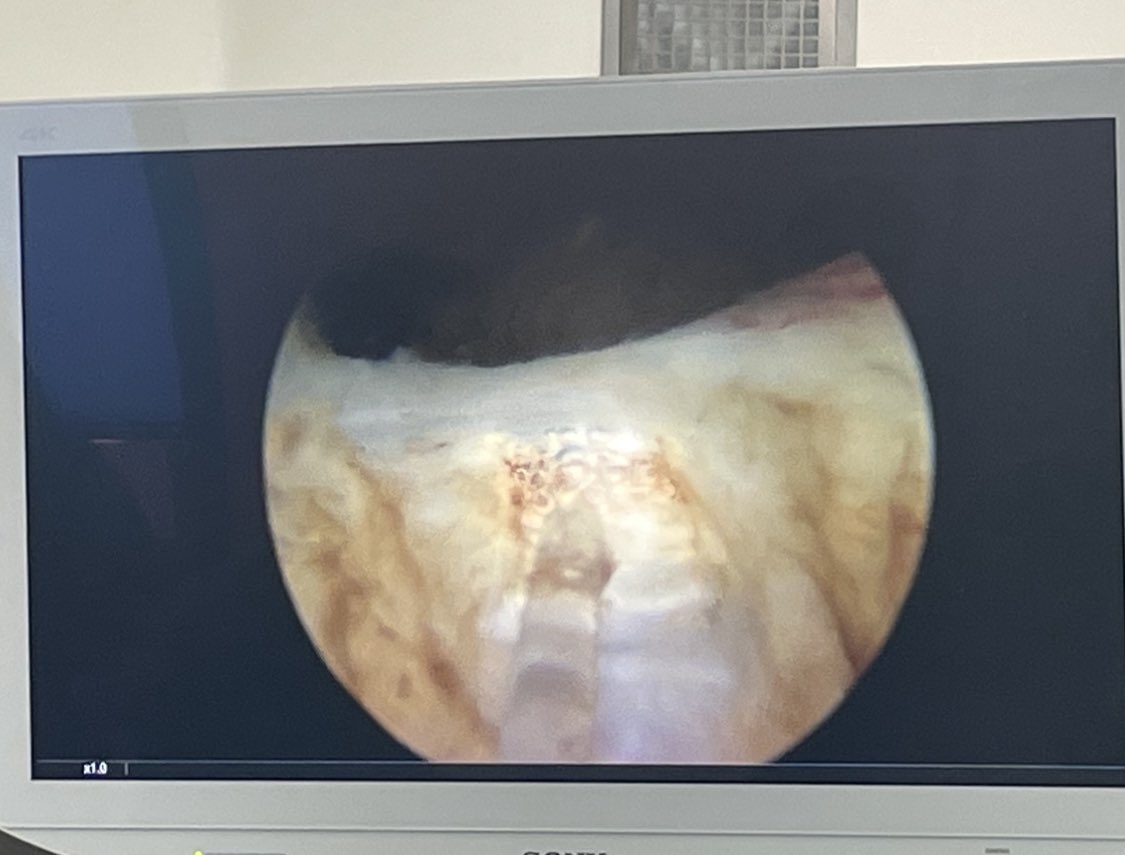

Thulium fiber lazer ile prostatın enükleasyonu ve mesane tümörü enblok rezeksiyonu ameliyatları Konya Şehir Hastanesi Üroloji Kliniği'nde bugünden itibaren yapılmaktadır. Destekleri için teşekkür ederiz. @saglikbakanligi @konyailsaglik @konyasehirhast

Today, we performed our first ThuFLEP cases in Konya City Hospital. We are grateful for their support @saglikbakanligi @konyailsaglik @konyasehirhast @msozkent